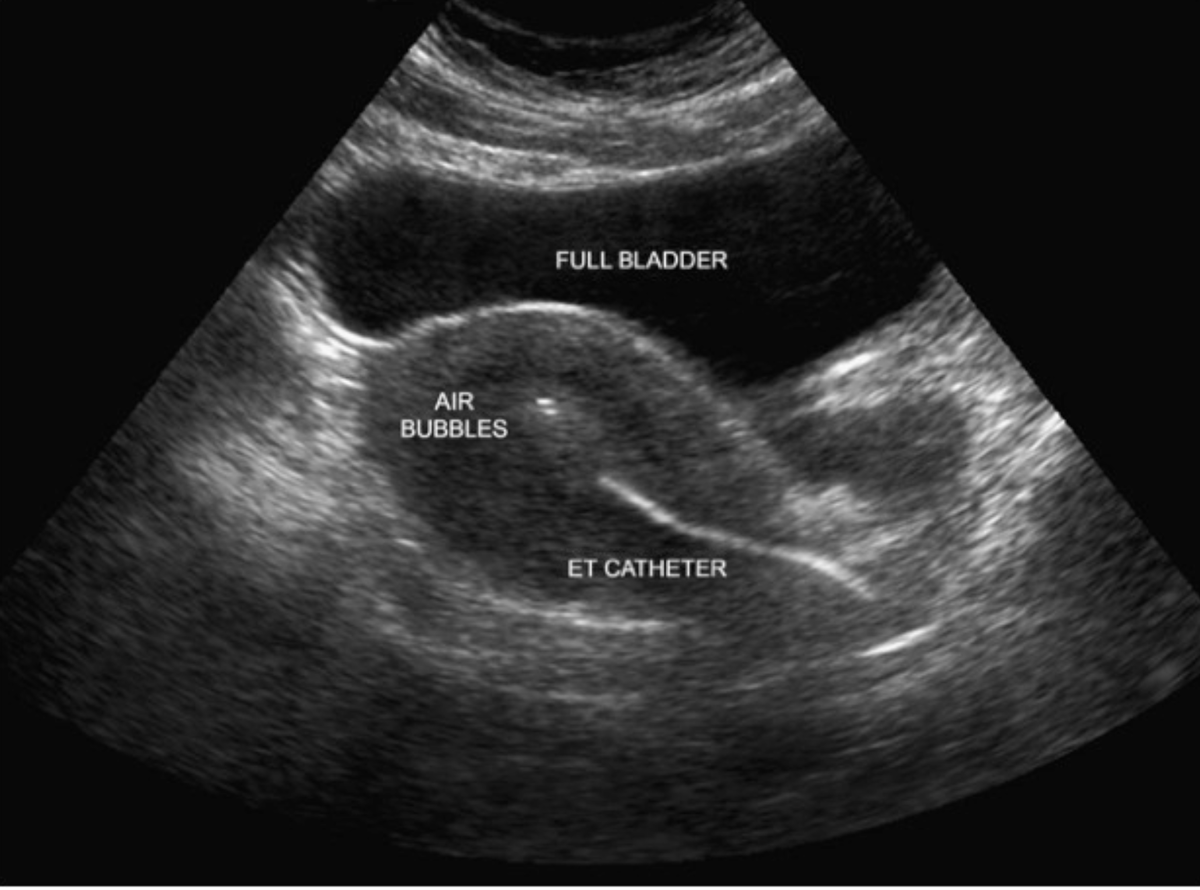

Цель успешного переноса эмбрионов - доставить эмбрион(ы) в матку, не повредив их. Исторически перенос эмбрионов осуществлялся с помощью специального катетера, который продвигался до контакта с верхней частью полости матки (дном матки), затем катетер выводился на 5-10 мм перед выбросом эмбрионов. С использованием ультразвука стало очевидно, что при такой «слепой» технике катетер плохо устанавливается в 20% случаев. За последние два десятилетия эта техника была в значительной степени усовершенствована ультразвуковым наведением.

Вот несколько интересных фактов о переносе эмбрионов с ультразвуковым наведением:

6. Полный мочевой пузырь действует как «ультразвуковое окно» и облегчает визуализацию с помощью трансабдоминального зонда. Он также помогает выпрямить маточно-цервикальный угол и облегчить введение катетера, особенно при сильно антевертированной матке.

7. Пациенткам нравится визуализация последнего этапа, когда они видят «вспышку» от воздуха и жидкости, окружающей эмбрион(ы). Это действительно здорово - визуализировать момент, когда вы (теоретически) беременны!